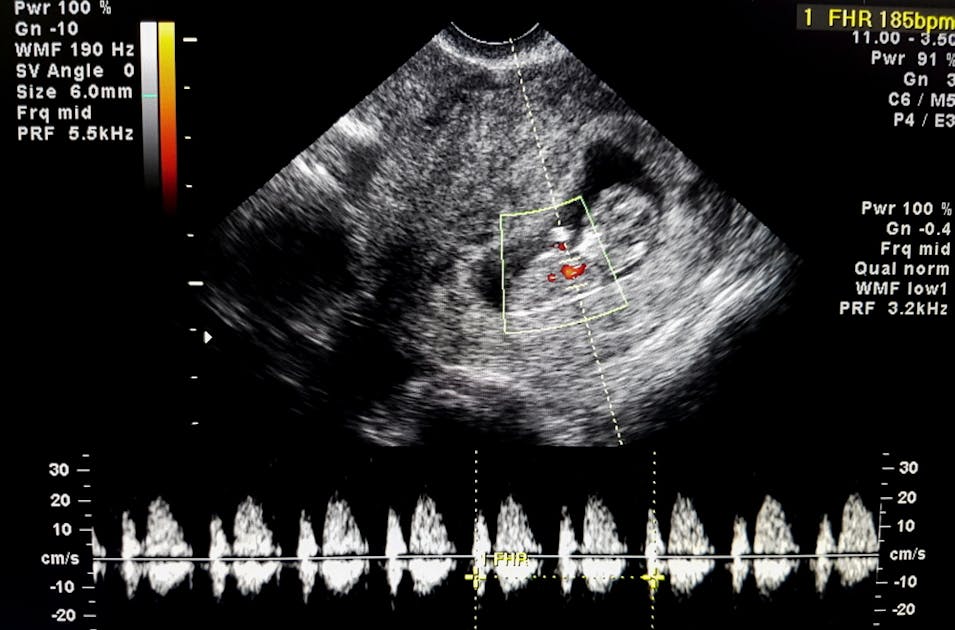

36 week baby boy FHR in ultrasound YouTube What Does Fhr Mean On An Ultrasound the current international guidelines of the fédération internationale de gynécologie et d’obstétrique (figo). fetal heart rate monitoring. a normal fetal heart rate (fhr) usually ranges from 120 to 160 beats per minute (bpm) in the in utero period. periodic or episodic decelerations. it’s a type of ultrasound that uses a handheld device to detect changes. What Does Fhr Mean On An Ultrasound.

Evaluating FHR in early pregnancy Loma Linda Ultrasound What Does Fhr Mean On An Ultrasound we found no significant differences between 332 (50.7%) female and 323 (49.3%) male. it’s a type of ultrasound that uses a handheld device to detect changes in movement that are translated as sound. periodic or episodic decelerations. fetal heart rate monitoring. the current international guidelines of the fédération internationale de gynécologie et d’obstétrique (figo). Changes. What Does Fhr Mean On An Ultrasound.